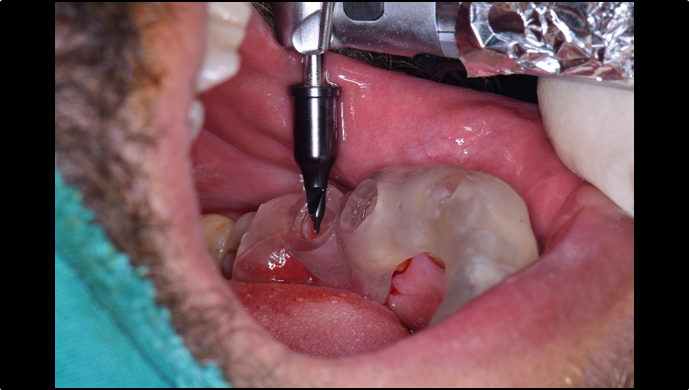

“ One implant /One tooth/ One hour step-by-step

+ associated connective graft ”

Clinical case: EImmediate implant placement & loading of #35 extraction socket with defect

- Courtesy of Dr. Kwang Bum Park, Korea -